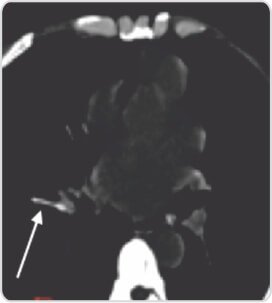

Linear hyperdense foreign body embolized into anterior segmental branch of right descending pulmonary artery

CT scan of thorax was done which revealed dislodged canula tip in anterior segmental branch of right descending pulmonary artery. The patient was planned for cardiothoracic surgery for removal of IV canula shaft. Before the surgery, the interventional radiologist’s opinion was taken, and the patient was taken up for fluoroscopy guided removal.

Under fluoroscopic guidance, the tip of the canula was identified as a linear filling defect in anterior segmental branch of right descending pulmonary artery.Usinga15mm endovascular snare, the tip of the IV canula was snared out without any complication. The patient was discharged on the next day